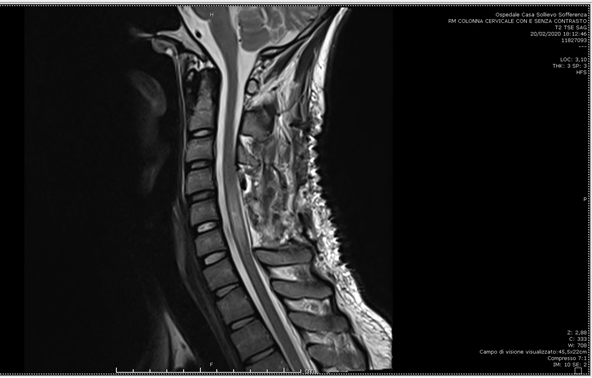

A new MRI (Figure 3) in the sagittal T2 STIR sequence showed increased dimensions of the collection extending from C7 up to C2 with increased evidence of the previous compressive findings together with a new hyperintensity of the posterior cervical spinal tract linked to the medullary impairment. The patient underwent emergency C4 to C6 laminoplasty to evacuate this space-occupying hematoma. During the operation, an acute-subacute hematoma located in the posterior part of the spinal canal was isolated.

Figure 3 MRI in the sagittal T2 STIR sequence showing increased dimensions of the collection extending from C7 up to C2 with increased evidence of the previous compressive findings.